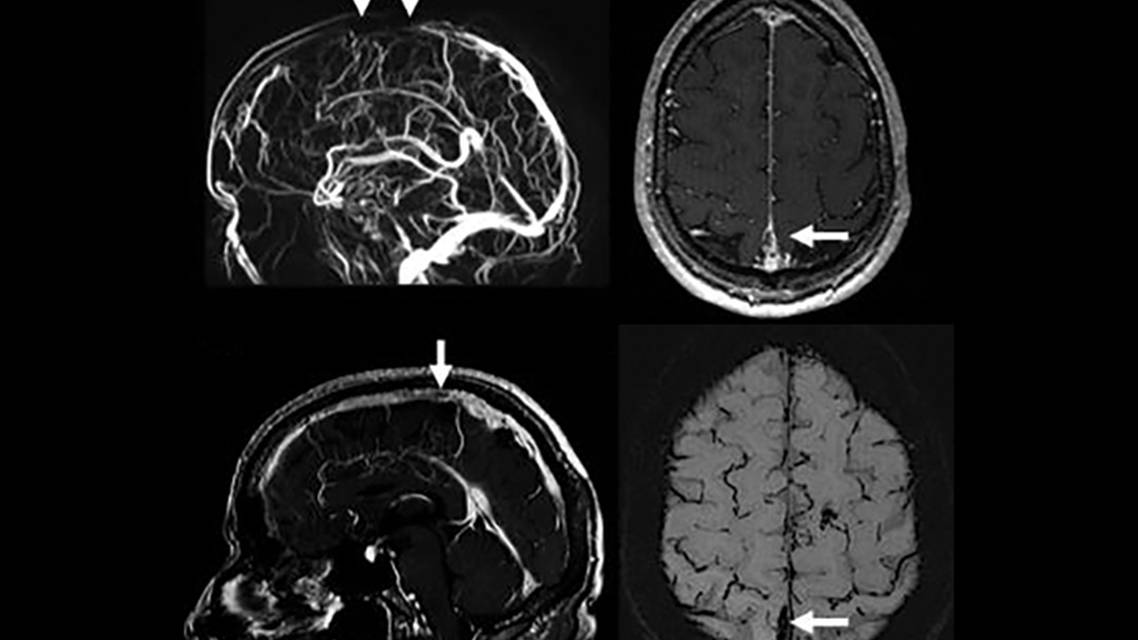

Risk factors for CVST include pregnancy/puerperium, use of estrogen-containing contraceptives, antiphospholipid syndrome, other inherited hypercoagulable conditions, hyperhomocysteinemia, infection, and malignancy.3 Direct signs of CVST are only evident on NCCT scans in one-third of cases; therefore, clinical suspicion may warrant contrasted CT venogram or MR venogram (Figure 1). Abnormalities on NCCT scans include hyperdensities in the dural sinus or linear hyperdensity caused by a thrombosed cortical vein. Evidence of venous infarction occurs in about 20% to 50% of cases, characterized by lesions that cross arterial distribution or spare the cortex.5 CVST occurs most commonly in the superior sagittal sinus, transverse sinuses, and sigmoid sinuses, with one-third of cases involving multiple sinuses.6 Brain parenchymal lesions are best evaluated with MRI. Appropriate laboratory tests should include sedimentation rate, prothrombin time, and activated partial thromboplastin time.3 Prothrombotic conditions are seen in more than one-third of individuals with CVST and necessitate testing for thrombophilia, antiphospholipid syndrome, and hyperhomocysteinemia. If serum studies are unremarkable, it may be prudent to screen for underlying malignancy. Treatment is with anticoagulation, with data showing that low-molecular-weight heparin is safer and potentially more effective than unfractionated heparin.4 If clinical deterioration continues, direct catheter chemical thrombolysis or direct mechanical thrombectomy can be performed.3

![Figure 1: Sagittal sinus thrombosis. (A) MR venogram showing absent venous flow signal in the middle third of the superior sagittal sinus (white arrows); (B) axial gadolinium-enhanced T1-weighted MR scan showing an irregular filling defect of the superior sagittal sinus (white arrow); (C) sagittal gadolinium-enhanced T1-weighted MR scan also showing a focal filling defect indicating thrombus (white arrow); (D) axial susceptibility-weighted imaging showing low signal indicating blood products (thrombus) in the superior sagittal sinus (white arrow).

(From Practical Neurology, Wlivi L, Squitieri M, Cohen H, Cowley P. Werring, D. Cerebral venous thrombosis: a practical guide. 20: 356-367. Copyright © [2020]. Reprinted with the permission of BMJ Publishing Group Ltd.)](https://cdn.practicalneurology.com/cache/de/38/de38b1caa011e47ead7554789ee38099.png)